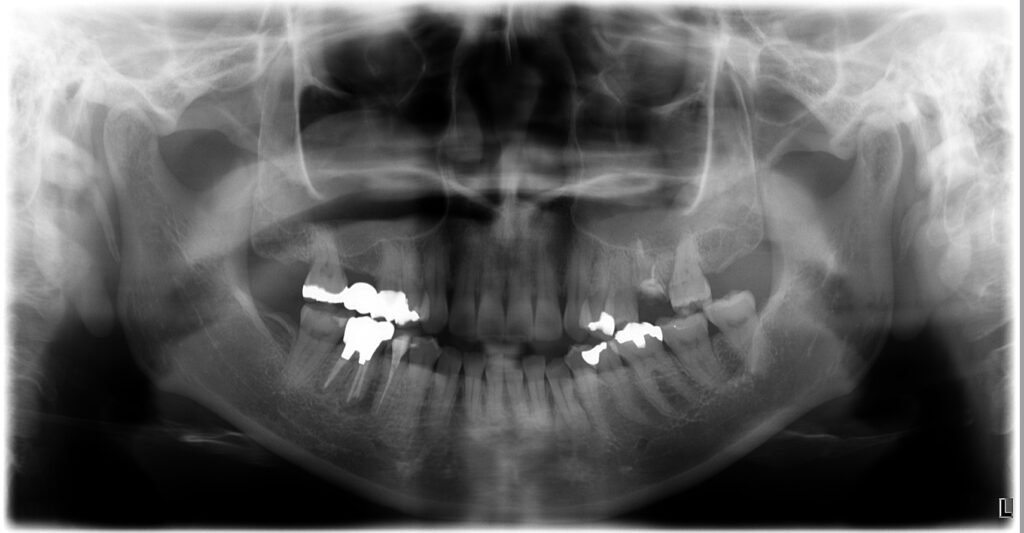

初診時の状態は以下の通りでした。

- 広範囲の二次カリエスで残根状態

- 咬合面の高さが低く保持力が不足

- レントゲンに亀裂を疑う像

- 歯肉の発赤・腫脹

- 何度も被せ物が脱離している既往

- 噛むと痛む

治療後の状態

治療後には、以下のような改善が見られました。

・ 痛み・腫れの消失

・ レントゲンで透過像が縮小し骨の回復

・ 歯肉が自然で健康的なラインに

・ セラミッククラウンが自然に適合

・ 咬合が安定し噛みやすくなる

外科なしでここまで改善できるのは、

根管治療・補綴・咬合の3つを総合的に設計しているからこそ です。